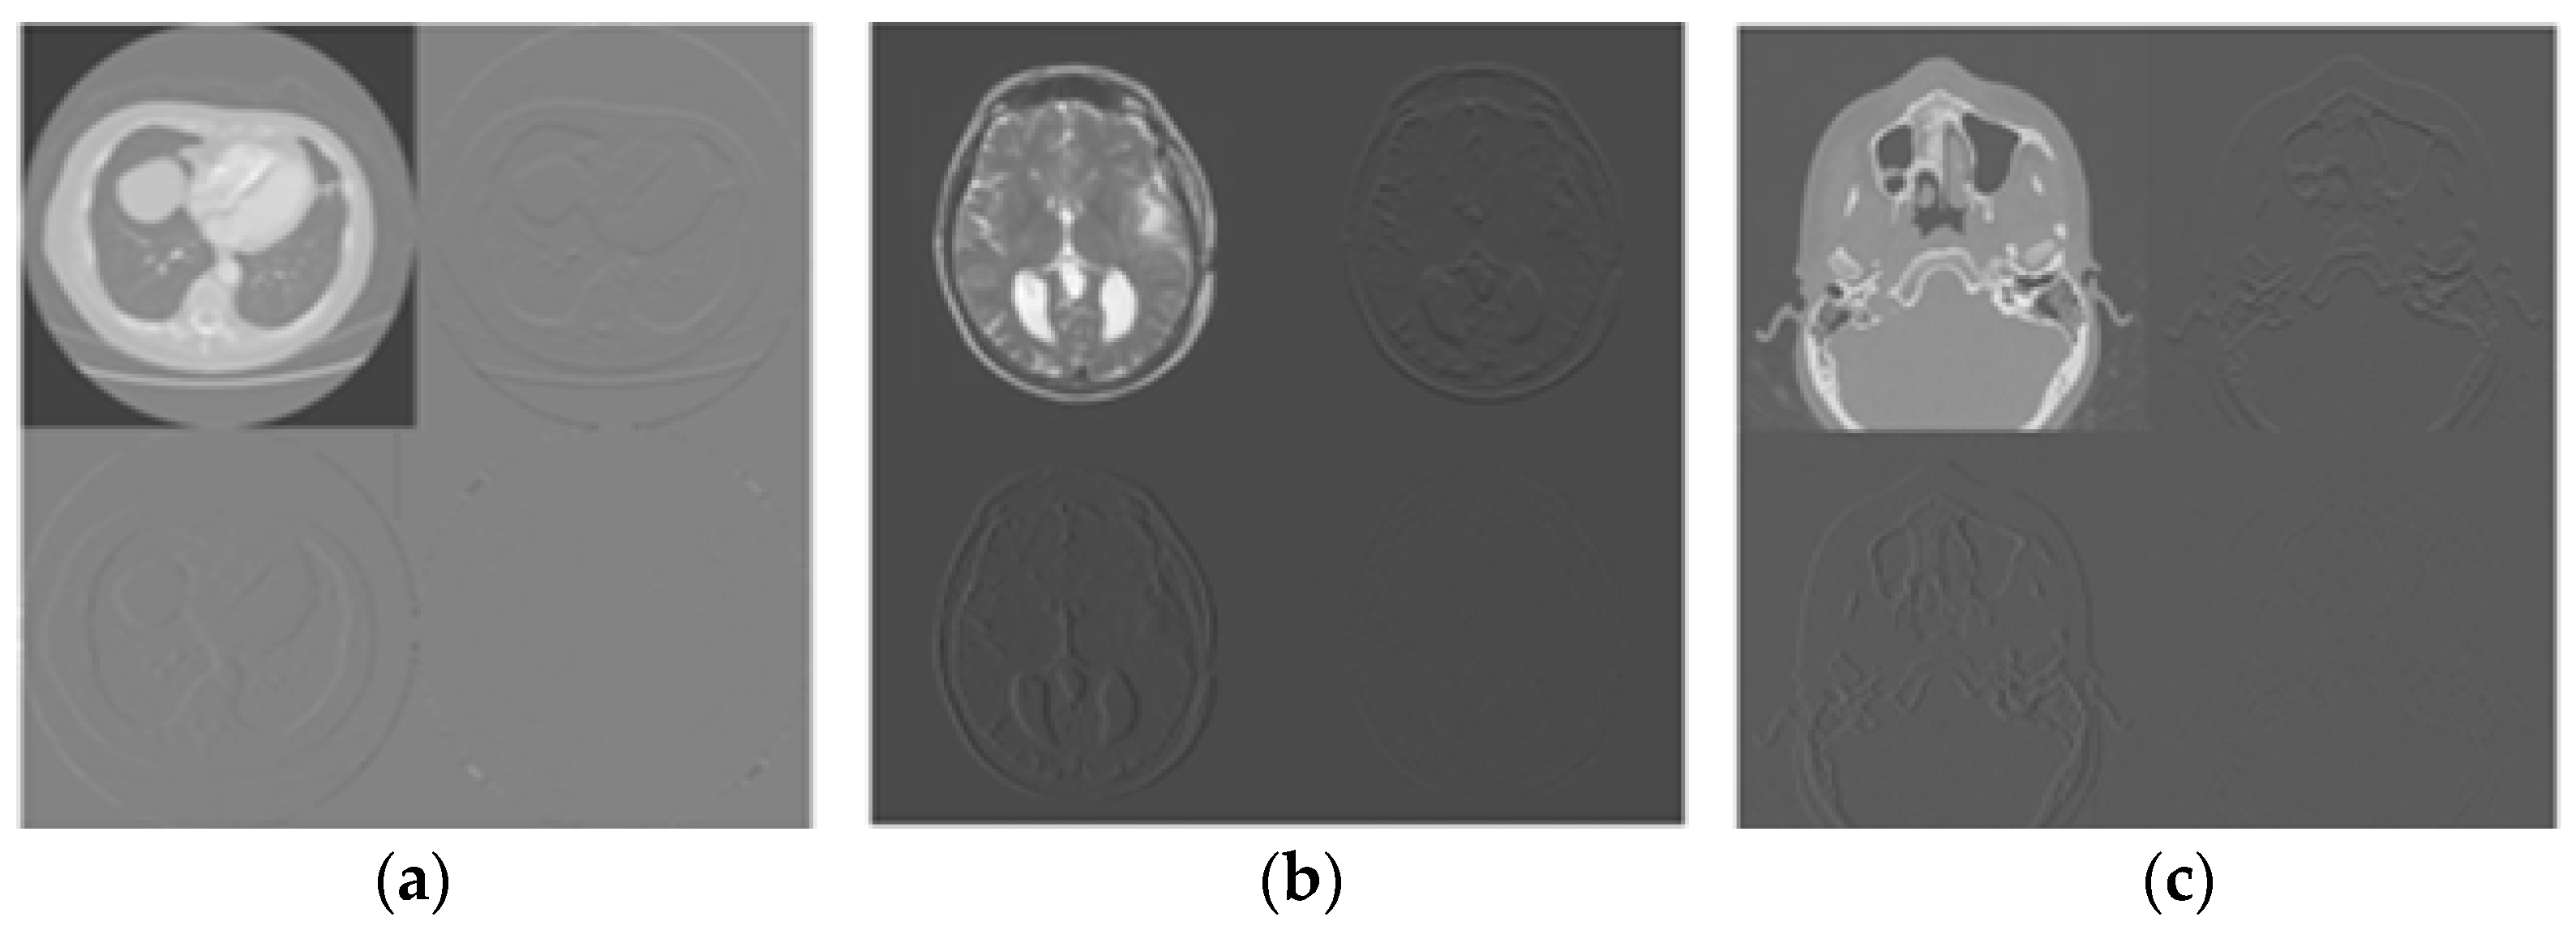

Figure 6 shows the test images. Figure 7 shows the few decomposed images using lifting. Figure 8 and Figure 9 show the watermarked images along with PSNR, MSSIM, and ‘K’ values and also the restored images, respectively. From Figure 8 and Figure 9, it is cleared that the watermark is embedded in the DICOM host image without decreasing the fidelity/quality of the image. Moreover, the image is restored completely by the proposed scheme.

Figure 7. Decomposed host images using lifting based DWT: (a) Lung, (b) MRI-1, (c) MRI-2.